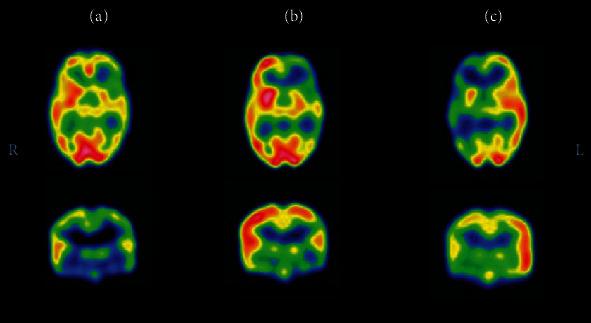

Up to 30% of patients with epilepsy may not respond to antiepileptic drugs. Patients with drug-resistant epilepsy (DRE) should undergo evaluation for seizure onset zone (SOZ) localization to consider surgical treatment. Cases of drug-resistant nonlesional extratemporal lobe epilepsy (ETLE) pose the biggest challenge in localizing the SOZ and require multiple noninvasive diagnostic investigations before planning the intracranial monitoring (ICM) or direct resection. Ictal Single Photon Emission Computed Tomography (i-SPECT) is a unique functional diagnostic tool that assesses the SOZ using the localized hyperperfusion that occurs early in the seizure. Subtraction ictal SPECT coregistered to MRI (SISCOM), statistical ictal SPECT coregistered to MRI (STATISCOM), and PET interictal subtracted ictal SPECT coregistered with MRI (PISCOM) are innovative SPECT methods for the determination of the SOZ. This article comprehensively reviews SPECT and sheds light on its vital role in the presurgical evaluation of the nonlesional extratemporal DRE.

多达 30%的癫痫患者可能对抗癫痫药物没有反应。耐药性癫痫(DRE)患者应进行发作起始区(SOZ)定位评估,以考虑手术治疗。耐药性非病变性颞叶外癫痫(ETLE)的病例在定位 SOZ 方面构成最大挑战,需要进行多次非侵入性诊断研究,然后再计划进行颅内监测(ICM)或直接切除。发作期单光子发射计算机断层扫描(i-SPECT)是一种独特的功能诊断工具,它使用在癫痫发作早期发生的局部高灌注来评估 SOZ。减去发作期 SPECT 与 MRI 配准(SISCOM)、统计发作期 SPECT 与 MRI 配准(STATISCOM)和 PET 发作间期减去发作期 SPECT 与 MRI 配准(PISCOM)是用于确定 SOZ 的创新 SPECT 方法。本文全面回顾了 SPECT,并阐明了其在非病变性颞叶外 DRE 术前评估中的重要作用。